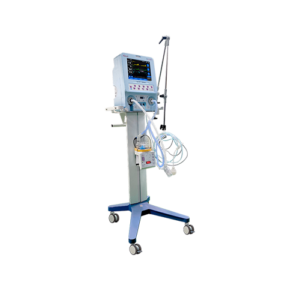

BC 585

Infant/Neonatal Breathing Circuit with Heated Wire for High Flow Oxygen Therapy